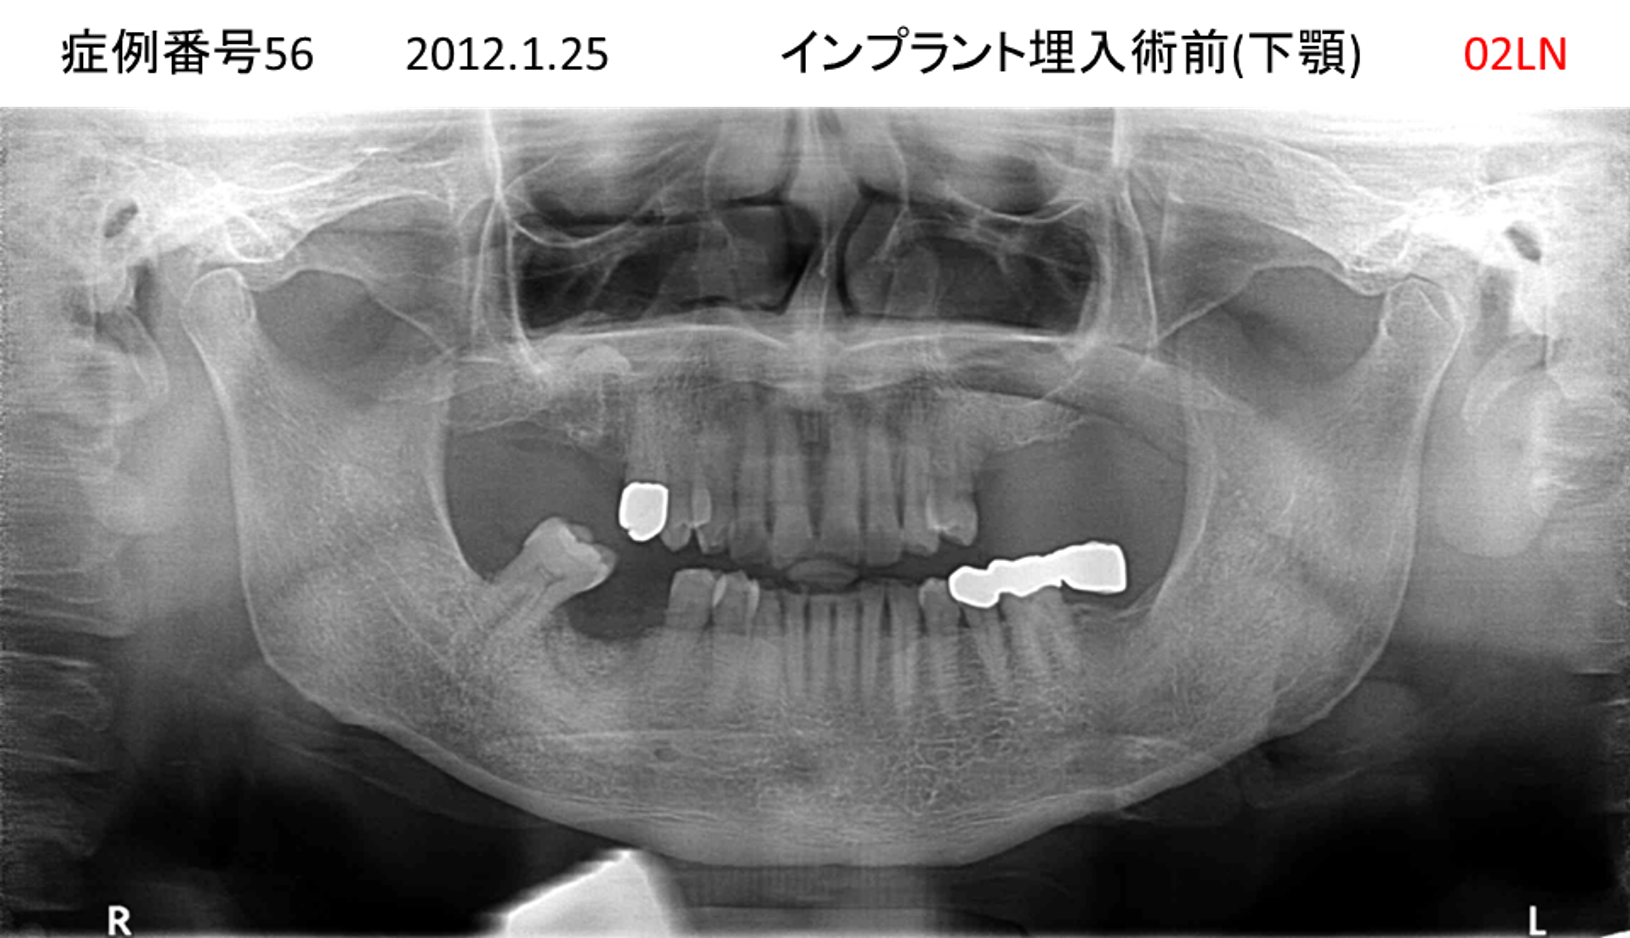

左下の歯が痛い患者様のインプラント症例

| 治療名称 |

インプラント |

| 治療費用 |

330万円+税 |

| 治療期間 |

4か月 |

| 患者さんの症状(主訴) |

左下の歯が痛い |

| 治療内容 |

サイナスリフト 抜歯即時インプラント |

| 治療結果 |

食事に困らない。見た目がとても良くなった。 |

| 治療の注意点(リスク/副作用) |

インプラントが壊れたら再治療が必要 |